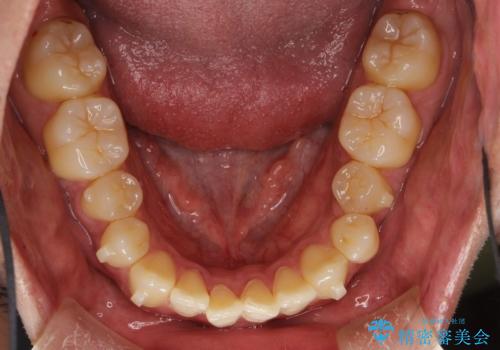

上下のがたつきをインビザラインで目立たない矯正

- 前歯のガタガタを主訴に来院されました。

上下の前歯のガタガタと左上の歯が反対にかんでいる状態でした。

上下の歯と歯の間をわずかに削り並べる計画としました。

目立たずに歯並びがよくなり、前歯に装着されたセラミックも壊さずに矯正治療が終了し満足していただけました。